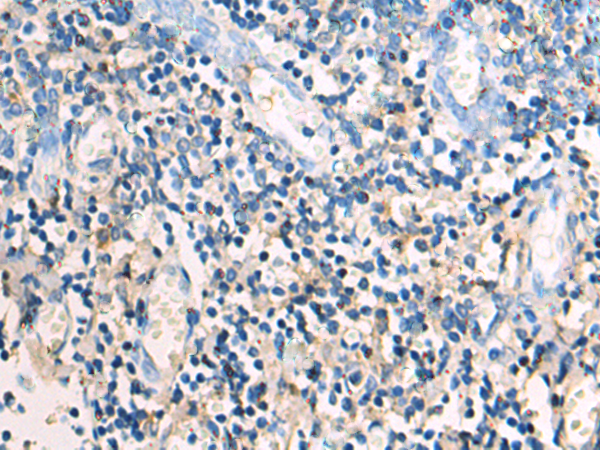

分类: 科研抗体货号: P05233别名: RNF35应用: IHC反应种属: Human